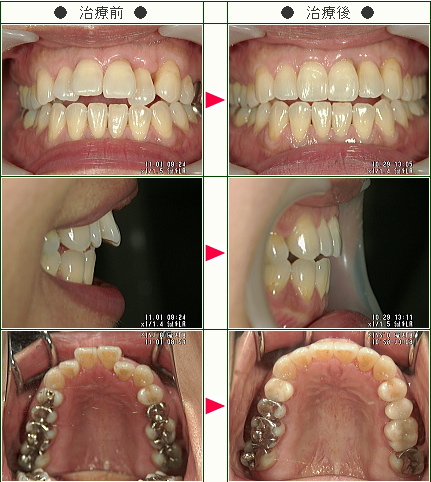

☆出っ歯矯正症例(E.H様 42歳 女性)

治療解説

主訴は前歯の前突感の改善です。

まずはワイヤーを使用して右上のデコボコを改善していきます。

ワイヤーの使用期間が約3か月で、マウスピースを3か月使用して歯並びを内側に傾斜して治療していきました。

トータルでの治療期間は6ヵ月で、調整料金を含めたトータルの治療費は29万円です。

上側だけの部分矯正では、噛み合わせは変わりませんので、見た目の改善だけの審美治療になります。

部分矯正において、ワイヤーでデコボコを改善するだけだと、矯正前よりも少しだけ前方に出てしまうため、歯の隣接面を少し削ることで前歯の前突感を改善していきます。

どこまで前歯を中に入れたいかで、隣接面を削る量は患者様の判断で決まります。

また歯を削らないでデコボコを治すだけですと、デコボコのある間にブラックトライアングルという隙間も残るため、ブラックトライアングルを減らすという目的のためにも前突感を改善するためにもその部分の隣接面を削って内側へ入れていきます。